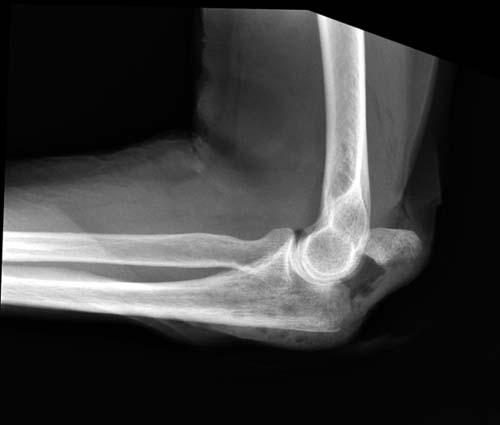

Обстоятельства дела. Пациентка Ш., 85 лет, поступила в отделение с оскольчатым переломом локтевого отростка с диастазом отломков. Из сопутствующей патологии: гипертоническая болезнь III ст.Б, АГ III ст, сахарный диабет, варикозное расширение вен н/конечностей, костный анкилоз левого локтевого сустава в порочном положении (после травмы более 30 лет назад). При более детальном осмотре рентгенограмм выявлен многооскольчатый перелом локтевого отростка с диастазом отломков, остеопороз (см. фото 1,2).

1) перелом - не оскольчатый, а раздробленный, с повреждением большей части локтевого отростка (С2 по А0, Тип IIIB по Mayo) с явлениями остеопороза, сминания промежуточных костных фрагментов. Подтверждением этому является наличие промежуточных костных фрагментов неопределенной формы, несоответствующей суставной части локтевого отростка, а также хорошо видимый передний подвывих костей предплечья (см. фото 2).